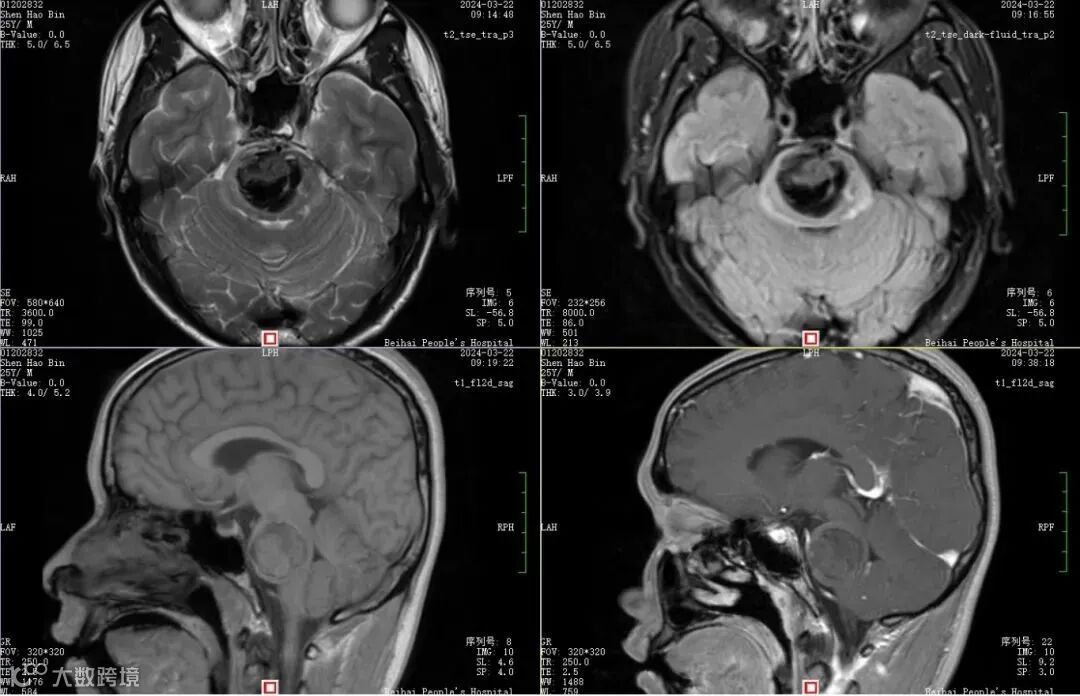

术前磁共振提示海绵状血管瘤合并出血